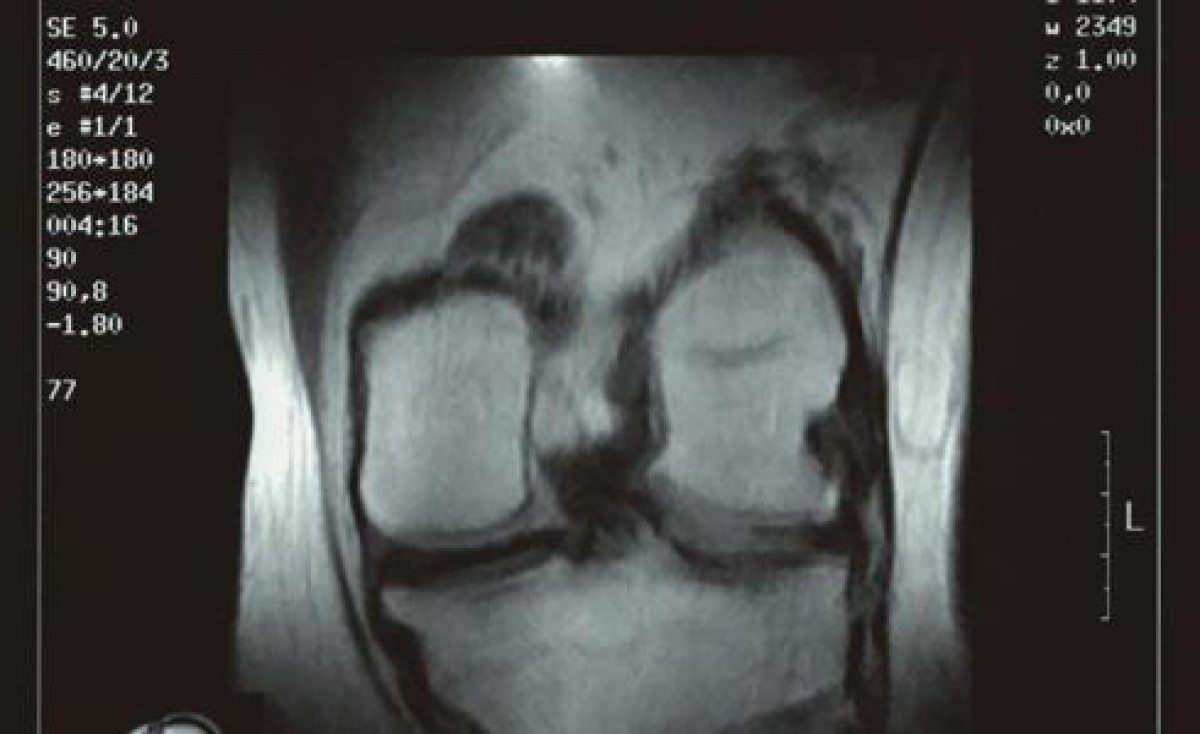

L'artrosi és una de la patologies més prevalents en la dona menopáusica

L'artrosi és una malaltia inflamatoria crònica que afecta a tota l'articulació. El 80 per cent de les dones menopáusicas sofreix dolor articular d'origen artrósico, de les quals el 50 per cent ho defineix com a insuportable o important. A part del dolor, altres símptomes són la limitació de la mobilitat, inflamació, cruixits en l'articulació afectada i rigidesa.